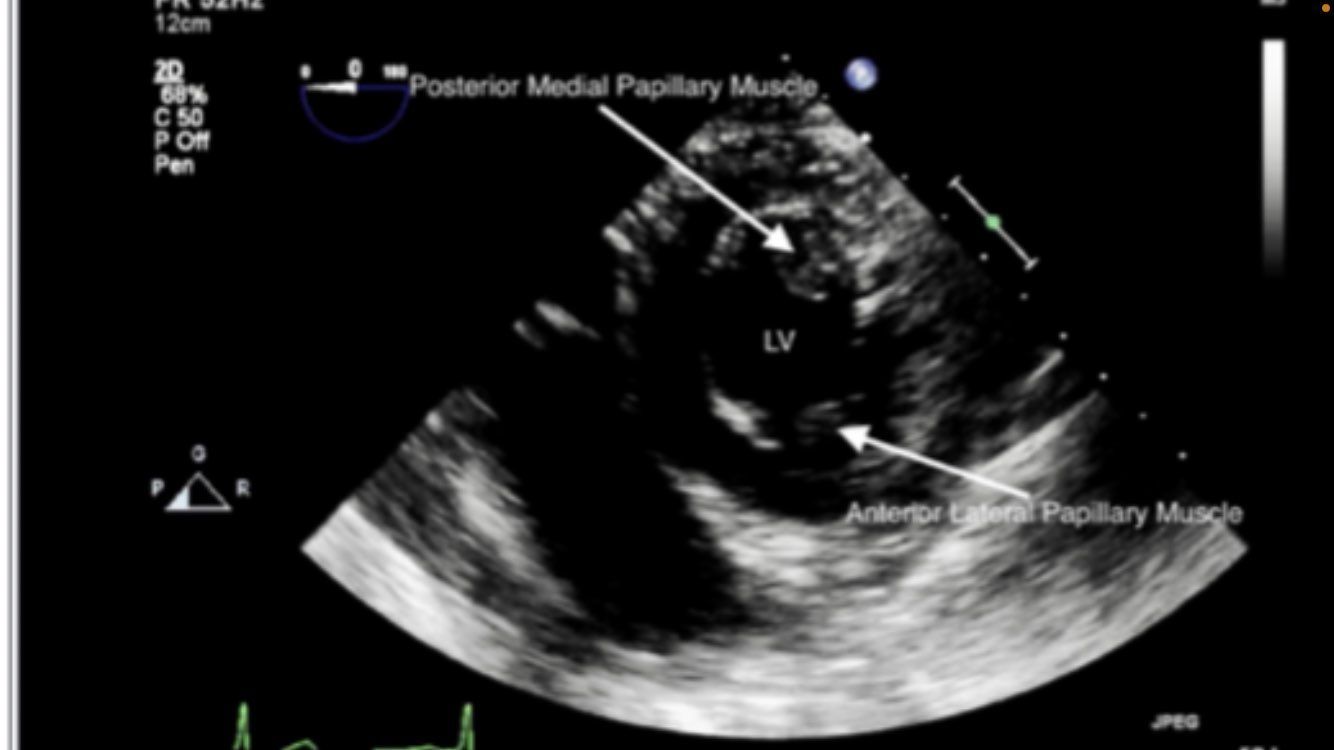

transgastric midpapillary SAX

transgastric mid SAX view